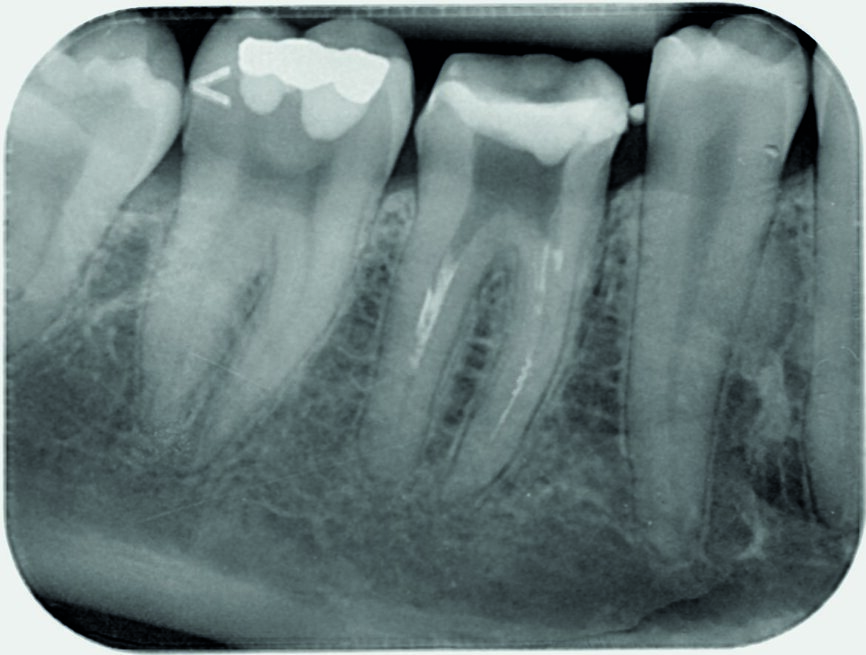

The calcium hydroxide paste was removed ten days later. The complete removal of paste from the root canal walls was accomplished by passive ultrasonic irrigation and 10% citric acid, using an endodontic tip (ESI, EMS) for more precise cleaning. Taking into consideration the extent of the apical root resorption, it was decided to perform orthograde MTA obturation of the distal canal space to arrest the resorption. The material was placed into the canals with the MAP System carrier (Produits Dentaires; Fig. 3) by the means of a 5 mm apical plug and was condensed vertically with a hand plugger. After radiographic examination of the accuracy of the apical plug (Fig. 4) and a setting period, the entire canal and the mesial canals were obturated with TotalFill BC (FKG Dentaire; Fig. 5). The orifices were adhesively sealed and the tooth was definitively restored with light-curing composite and prepared for a crown.

Fig. 4: Obturation of mesial canals and a 5 mm apical plug of MTA distally